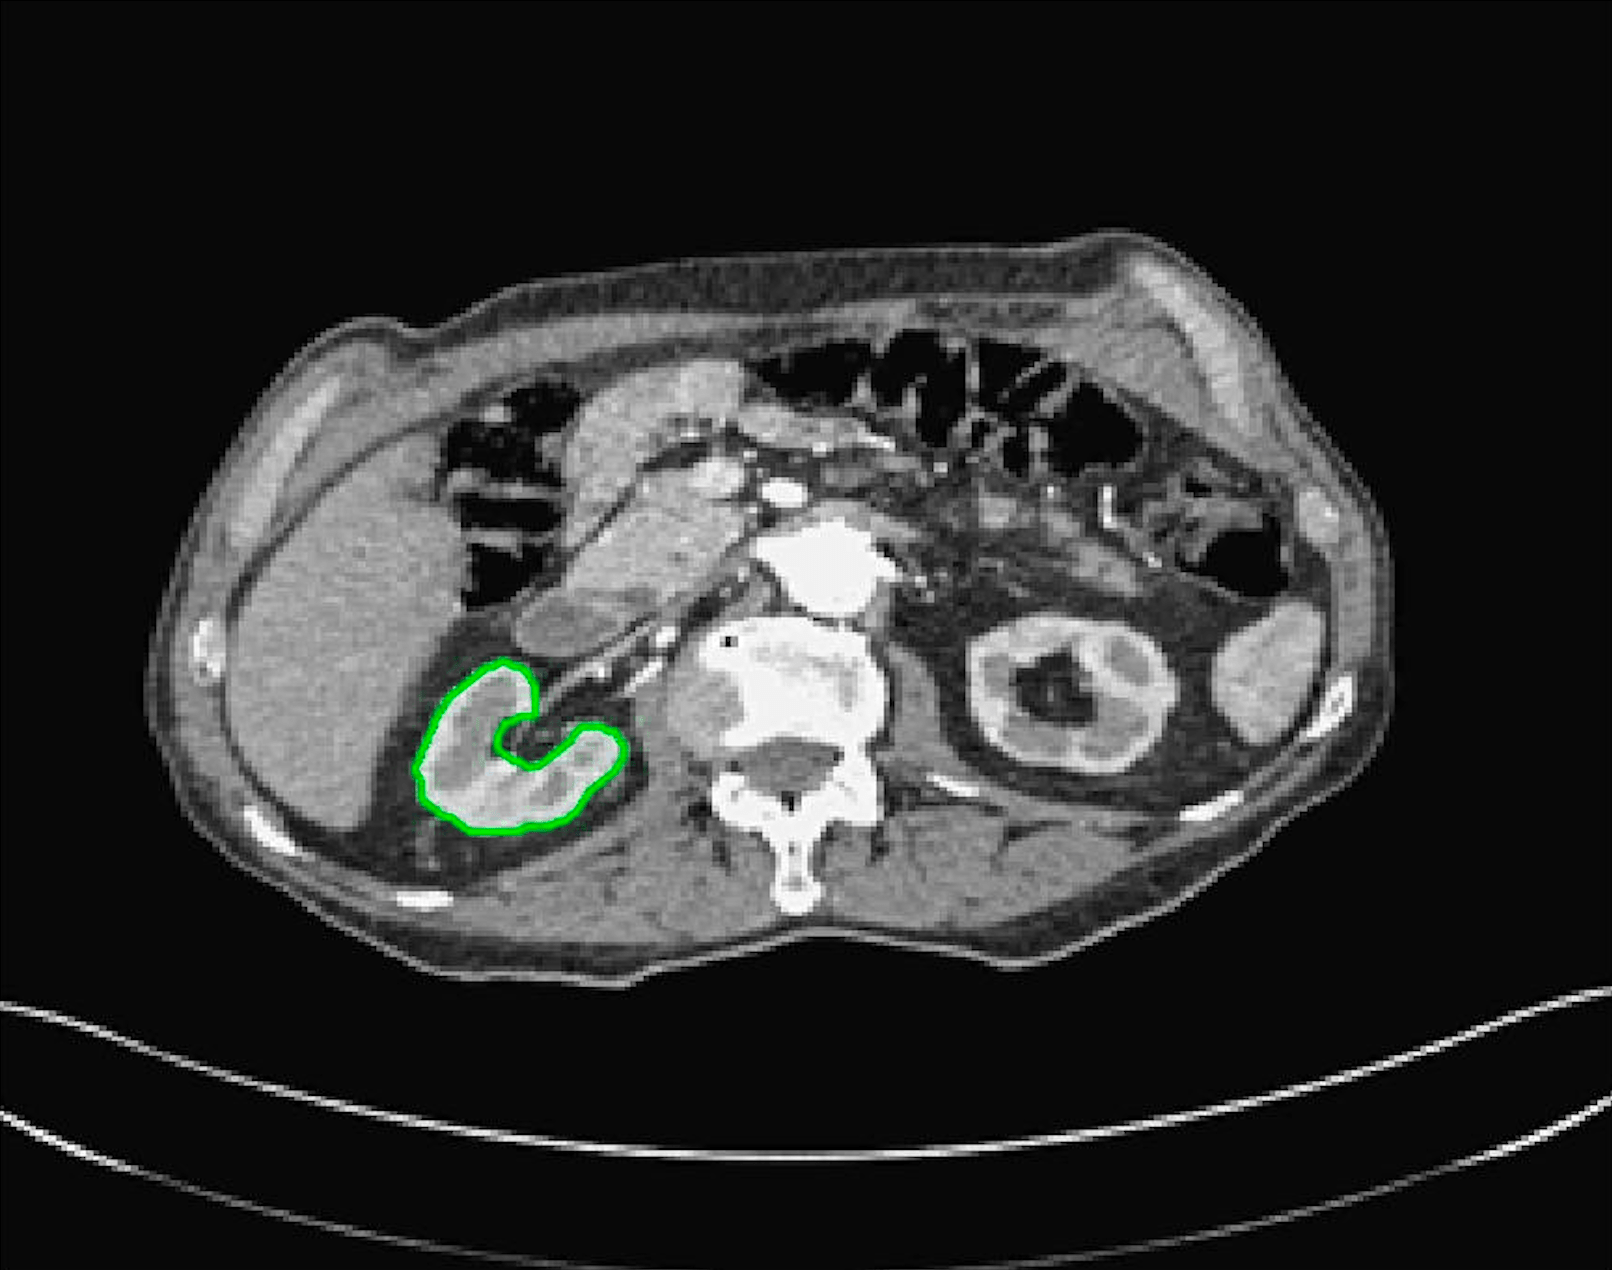

The motivation for this work comes from observing contradictions in using piecewise-constant intensity fitting terms in selective segmentation. Whilst good results are possible with this approach, the exceptional cases lead to severe limitations in practice. This is quite common in medical imaging as demonstrated in Fig. 1, where the target foreground has a low intensity. Given that the corresponding background includes large regions of low intensity, the optimal average intensities for this segmentation problem are and . For cases where , we see that by (1), almost everywhere in the domain . This means that it is very difficult to achieve an adequate result, without an over-reliance on the user input or parameter selection.

for and as defined in (33). This is consistent with respect to the intensities of the observed object and the concept of selective segmentation. In Fig. 3 we see the difference between CV and the proposed fitting terms for given user input on a CT image. For the CT image, the CV fitting terms are near 0 within the target region. This is despite there being a distinct homogeneous area with good contrast on the boundary. This illustrates the problem we are aiming to overcome. With the proposed fitting term this phenomenon should be avoided in cases like this. By defining as in (33) there is no contradiction if the foreground and background intensities of the target region are similar.